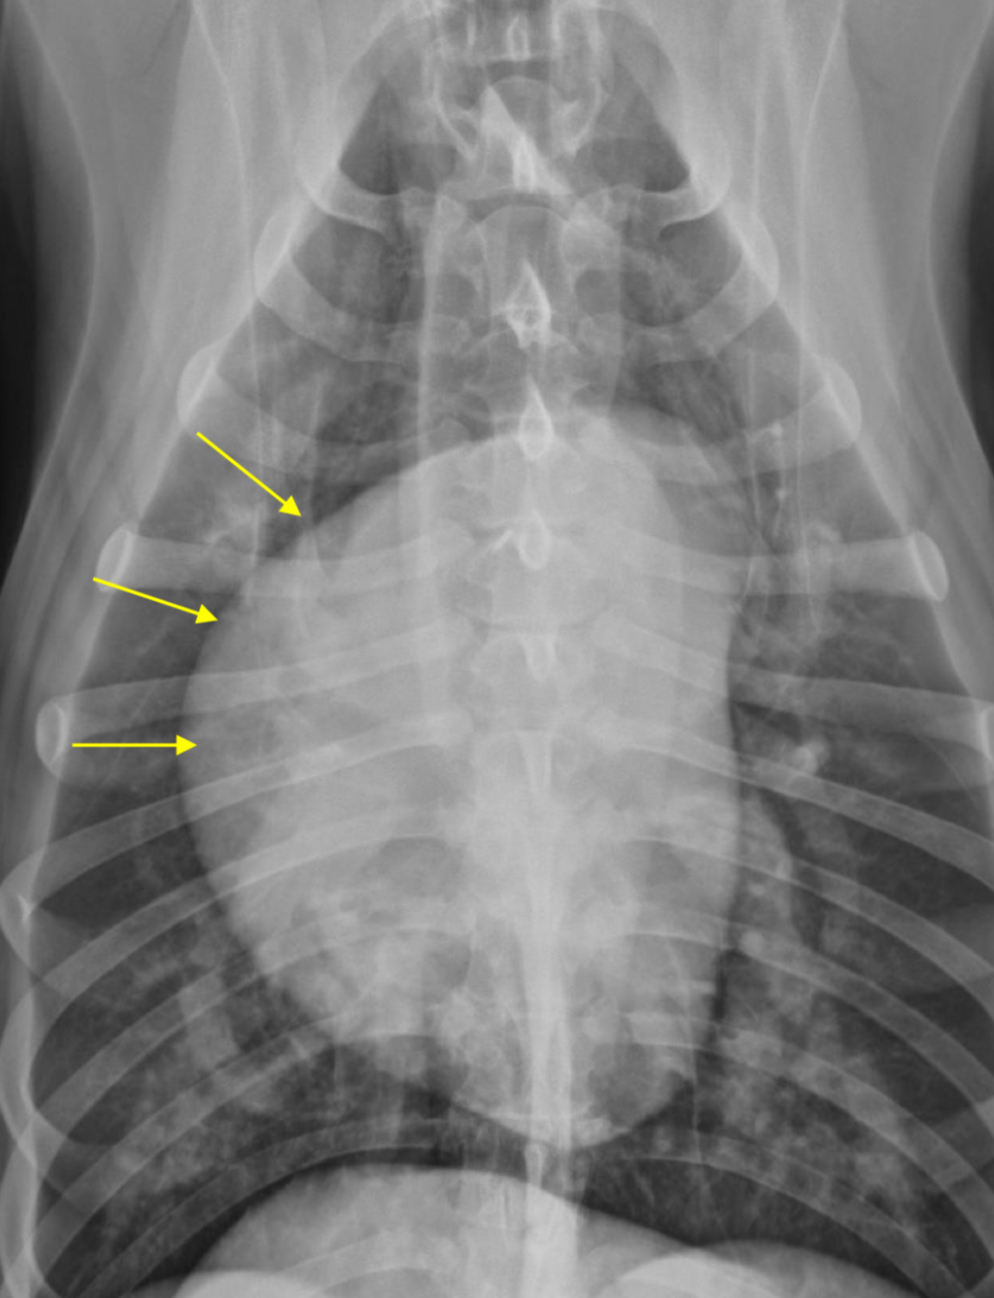

RAE feature on VD

Bulge at 9-11 o’clock region ± RVE bulge

What part of the heart is enlarged?

RAE

2 features of RVE on lateral

-wide cardiac silhouette

-cr.margin super bowed out —> increased sternal contact

What part of heart is enlarged?

RVE

2 features of RVE on VD

-bulge 5-9 o’clock

-reverse D

What part of the heart is enlarged